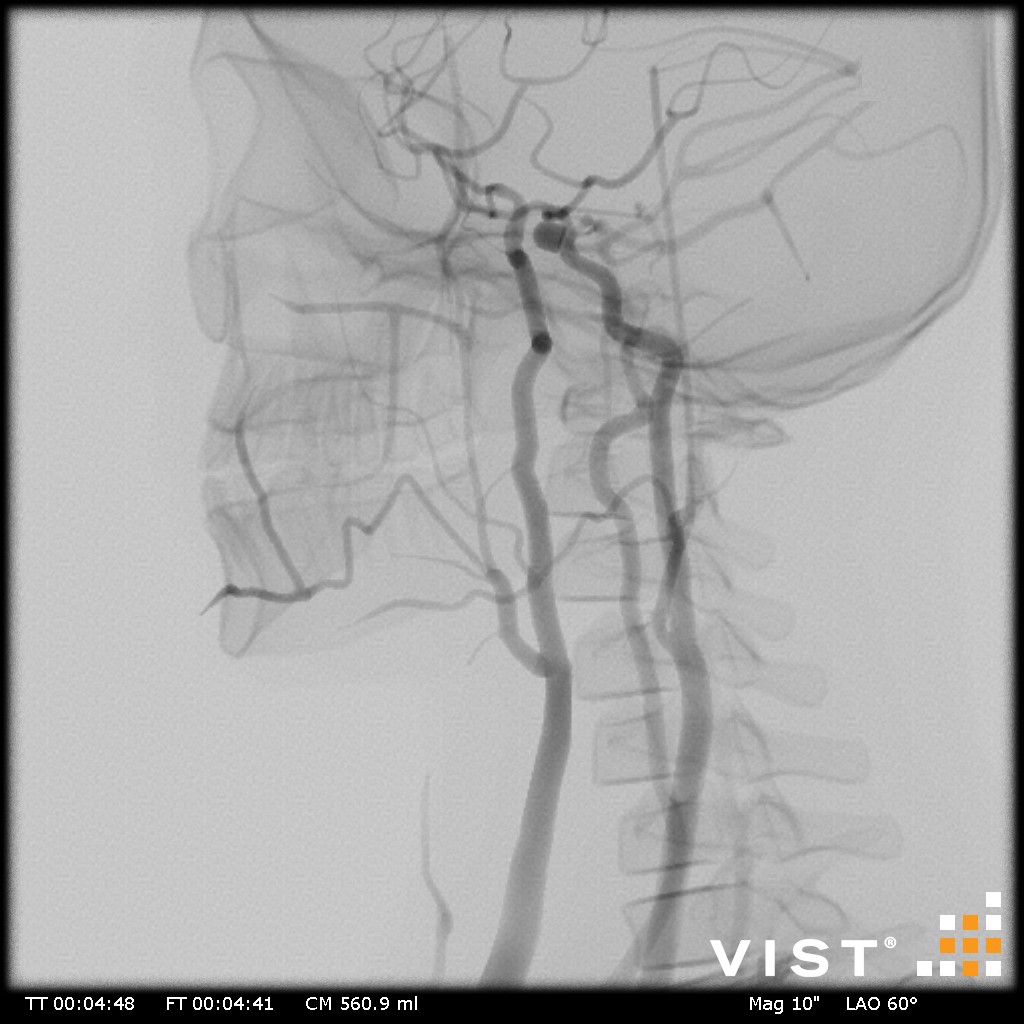

Simuladores Endovanculares.

Aquíhayuna listademódulosundonibles concatibles con el simulador vist g5(Versiónforporidenteyy lab,没有兼容的孔血管y vist灯)。Esta listaestántancoreeevolución,没有Dude en advertarla promicy ... los dutallesestándisponibles haciendo clic en eltítulodelmódulo(网站蒙黛尔,enInglés)